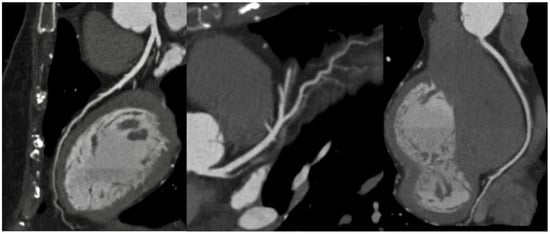

1.1. Computed Tomography